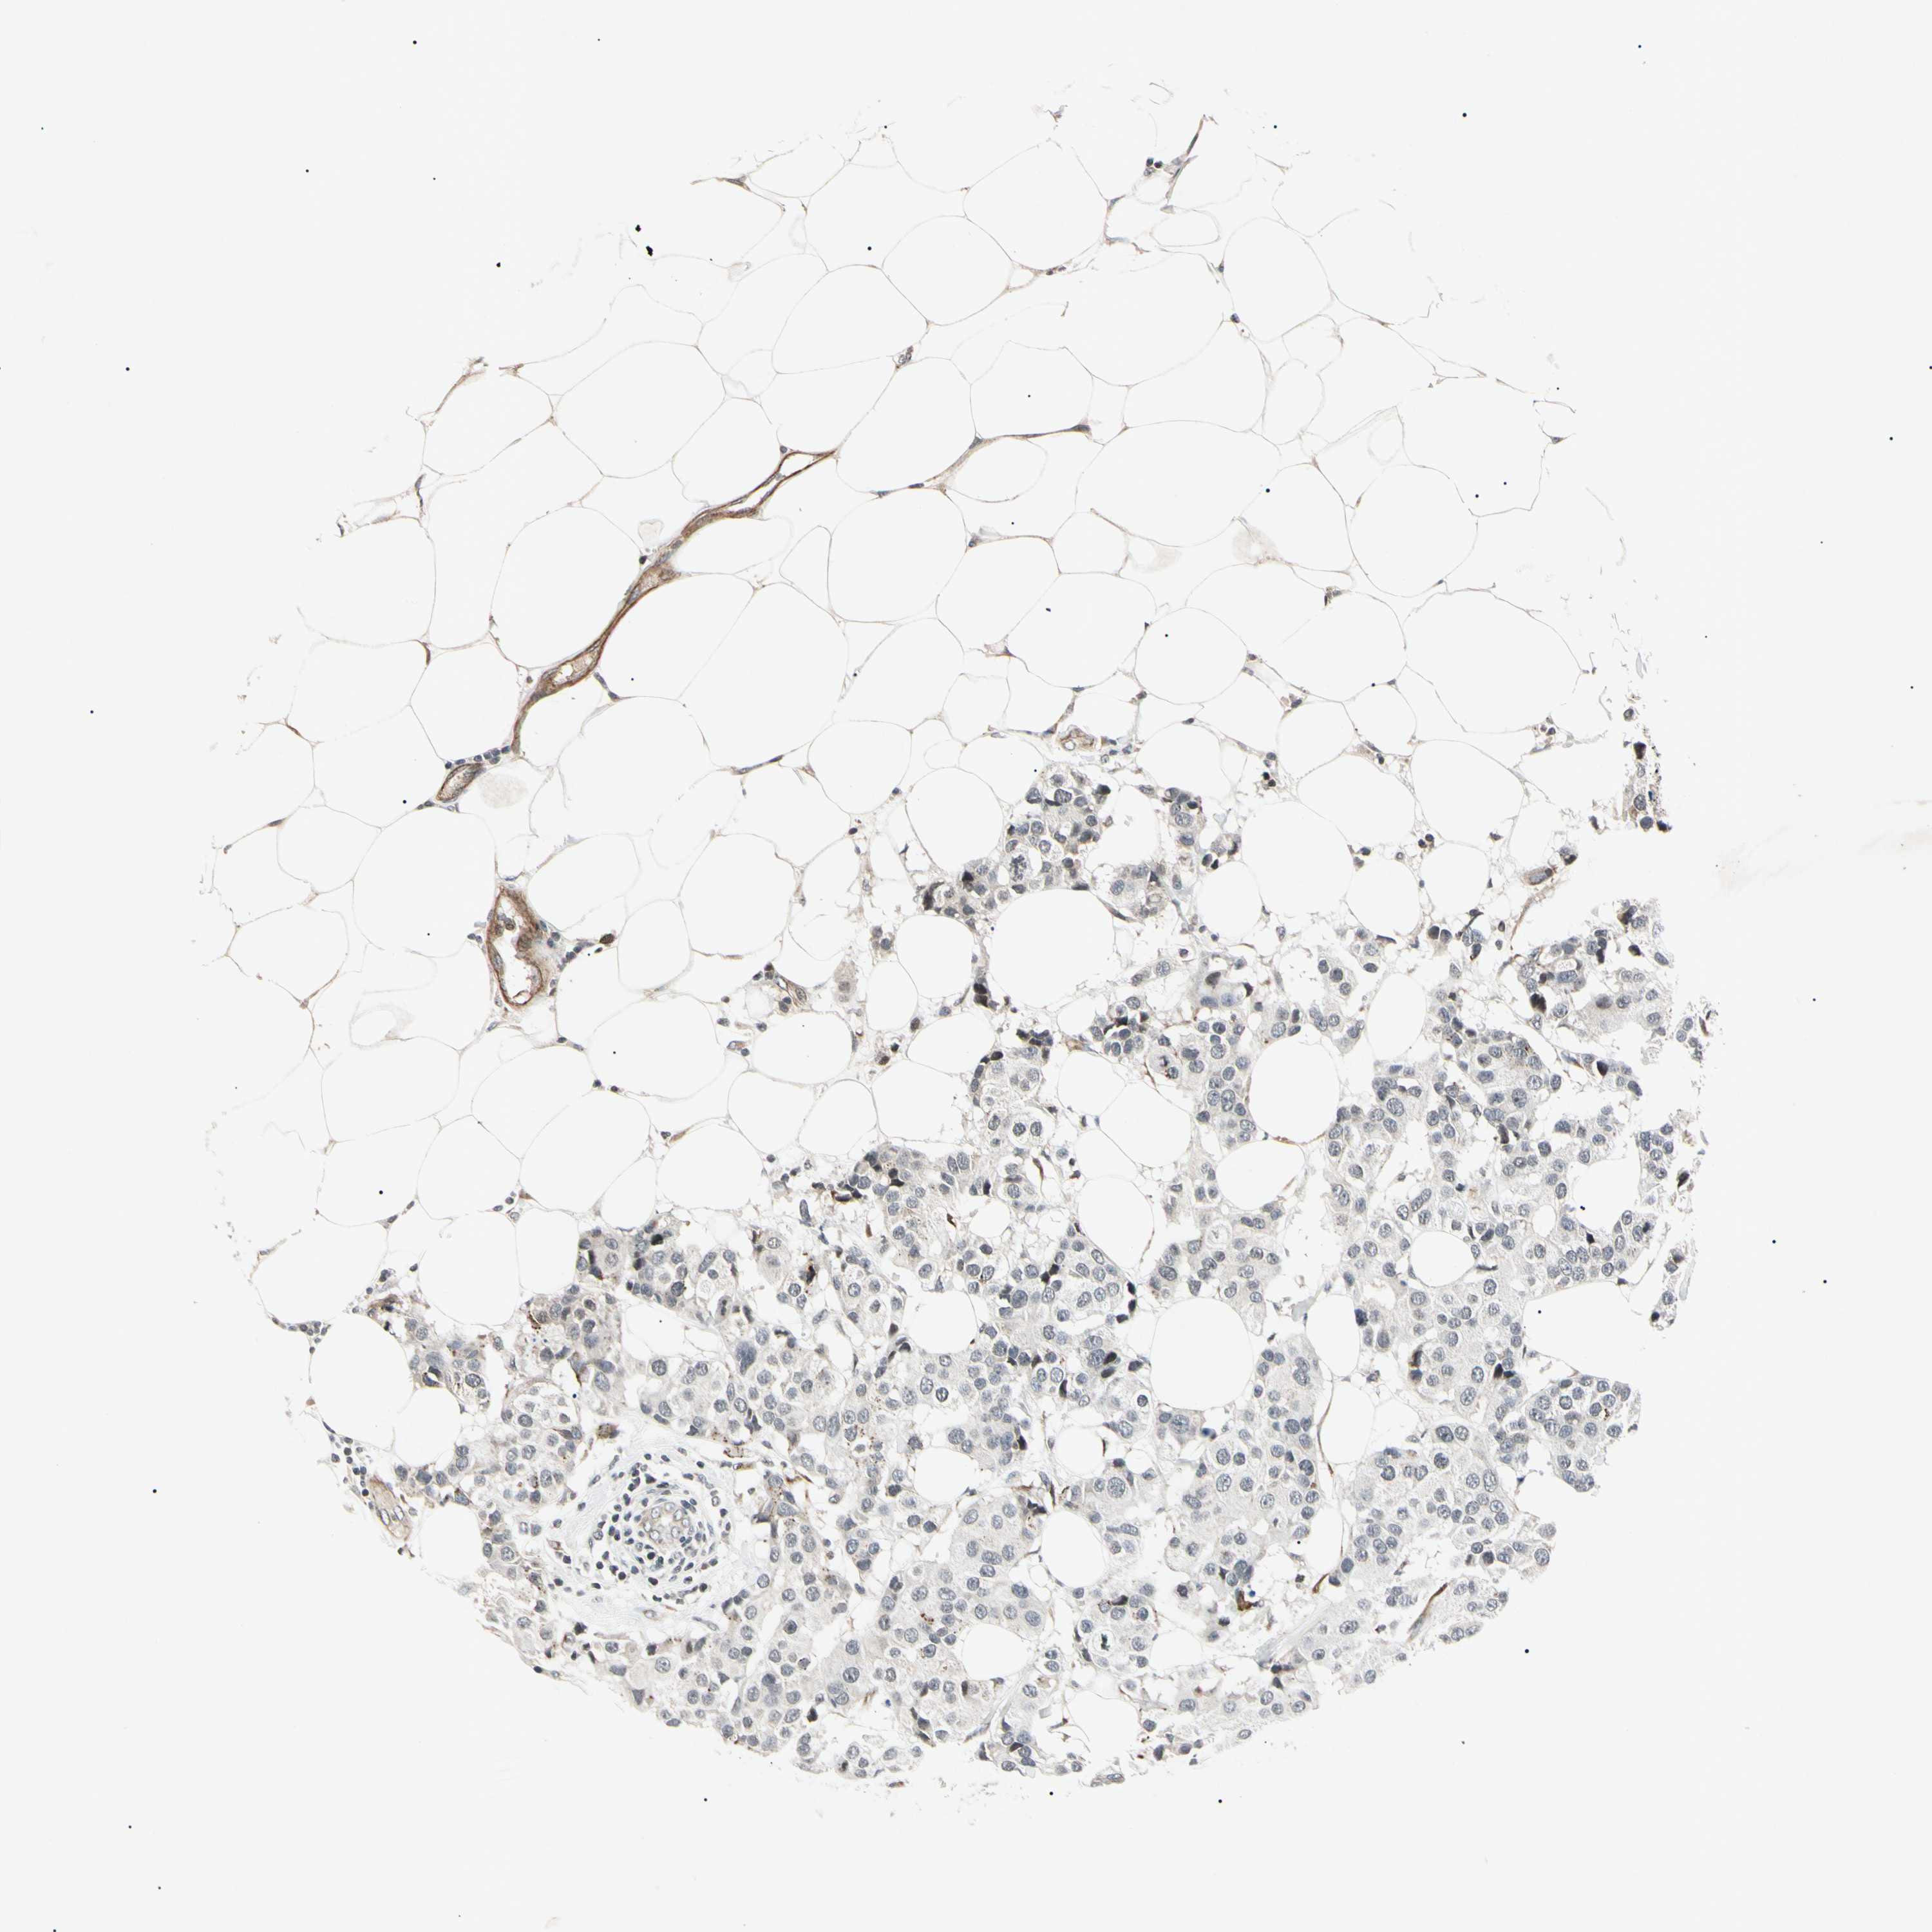

BRCA TCGA BRCA VALIDATION PROTEIN EXPRESSION